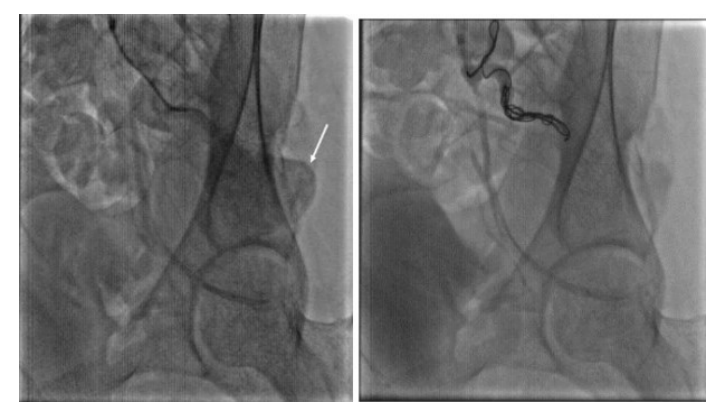

The first patient was a 44-year-old male without medical history, who developed an acute pain the day following an intramuscular injection in the right gluteal muscles, with paraesthesia and paresis of the right inferior limb. Three months later the patient presented in the emergency department due to worsening pain. Computed tomography scan (CT scan) identified a pseudoaneurysm in the right gluteal region arising from a branch of the right internal iliac artery which was most likely the inferior gluteal artery (IGA) (Figure 1). We performed a cross-over catheterisation and angiography of the right internal iliac artery which showed a contrast leakage of the IGA (Figure 2). We performed an embolization of the pseudoaneurysmal sac using 15x20 cm and 20x30 cm coils and embolization of the origin of the IGA using 12x30 cm and 10x20 cm coils (Figure 3). A CT scan was done 48 hours after and showed a profound hematoma of the right gluteal region without signs of contrast media extravasation. The day after, the patient benefited from drainage of the hematoma through a right retroperitoneal anterior incision (Figure 4). Transfusion of 2 units of blood was necessary after surgery. He had an uneventful recovery.